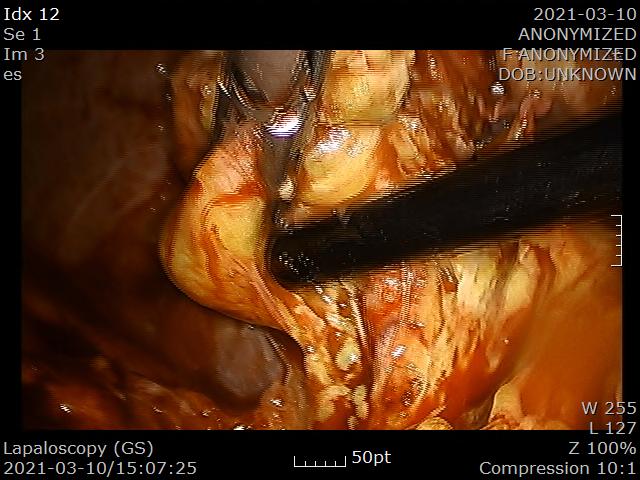

2021.3.10일 복강경 담낭절제를 시행했습니다.

PTGBD를 시행하고 나서 이후에 시행하는 담낭절제술은 기술적으로 어렵습니다. 염증이 가라앉으면서 조직이 유착되고 섬유화가 진행되어 조직을 박리하기가 아주 어렵기 때문입니다.

담낭 전체에 섬유화가 심해 아주 딱딱합니다.

겨우 겨우 담낭관을 노출시키고 결찰합니다.

최종적으로 담낭관을 절제하고 결찰한 모습입니다.

담낭동맥 주변에서 출혈이 있어 지혈하는데 시간이 많이 걸렸습니다.